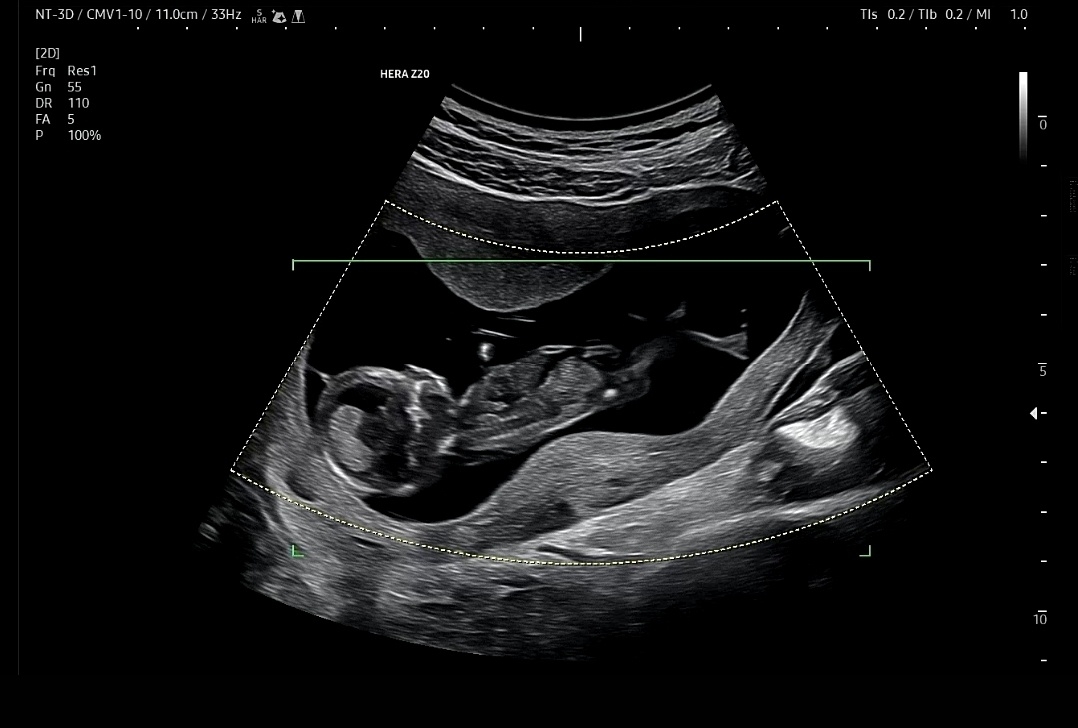

12주3일차에 1차 기형아 검사하고왓어요ㅎ 잘움직이고 다리펴는게 어찌나 귀엽고 기특하던지요ㅎ 우리아가 롱다리다 하면서 신랑이랑 흐뭇

롱다리 아가ㅎ